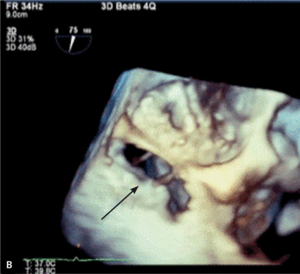

Rycina 2. Tętniak rzekomy lewej komory (strzałki) u pacjentki po implantacji protezy 2-dyskowej w pozycję mitralną.

Tętniaki rzekome lewej komory serca (left ventricular pseudoaneurysm, LVPA) są rzadkim, lecz bardzo poważnym powikłaniem zarówno zawału mięśnia sercowego, jak i leczenia operacyjnego. W tym drugim przypadku szczególnie wymiana zastawki mitralnej jest kojarzona ze zwiększoną częstością występowania LVPA. Pierwszy raz powikłanie to opisano w 1967 r. [11]. Częstość występowania tętniaków rzekomych u chorych po MVR szacuje się na 0,8-2% [12, 13]. Mają inną lokalizację niż tętniaki pozawałowe – LVPA po wymianie zastawki mitralnej stwierdza się zwykle w okolicy podpierścieniowej [14]. Do pęknięcia ściany lewej komory dojść może jeszcze na sali operacyjnej (tzw. wczesne pęknięcie), po kilku dniach (pęknięcie opóźnione), jak i później – po tygodniach lub miesiącach od operacji. Szacuje się, że późne pęknięcia odpowiadają za powstawanie około 10% wszystkich tętniaków rzekomych lewej komory serca po MVR [15]. Powstawaniu wczesnych LVPA sprzyja współistnienie trzech czynników: osłabiona struktura mięśniówki, agresywne manipulacje chirurgiczne i występowanie znacznych sił prowokujących przerwanie ciągłości mięśnia [16]. Jeżeli jama tętniaka jest wystarczająco duża (ryc. 2A, B), to mogą rozwinąć się objawy kliniczne zbliżone do obserwowanych w niedomykalności zastawki mitralnej. Rokowanie jest jednak określone przede wszystkim przez naturę tętniaka. Ograniczona jedynie osierdziem jama LVPA z dużym prawdopodobieństwem (szacowanym na około 45%) może pęknąć [17], co może mieć fatalne konsekwencje. Tętniaka rzekomego różnicować należy z przeciekiem okołozastawkowym, dysfunkcją protezy i przeciekiem między lewą komorą serca a zatoką wieńcową. Leczeniem z wyboru jest naprawa chirurgiczna. W zależności od lokalizacji tętniaka [18] może być ona wykonana z dostępu przez lewy przedsionek (typ 1 LVPA w tylnej części bruzdy przedsionkowo-komorowej) lub od strony epikardium, bez otwierania jam serca (tętniak ograniczony do miokardium [typ 2], powstały wskutek pęknięcia ściany tylnej u podstawy mięśnia brodawkowatego, oraz typ 3 LVPA, do powstania którego dochodzi w wyniku pęknięcia w lokalizacji między typem 1 i 2, czasami możliwy jest dostęp z lewej torakotomii). W przypadku tętniaka rzekomego o wąskiej szyi możliwe jest zamknięcie przezskórne [19].